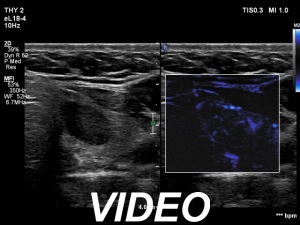

Ultrasonography. The thyroid was echonormal. There was a moderately hypoechoic lesion in the lower pole of the right lobe. The lesion presented no suspicious findings.